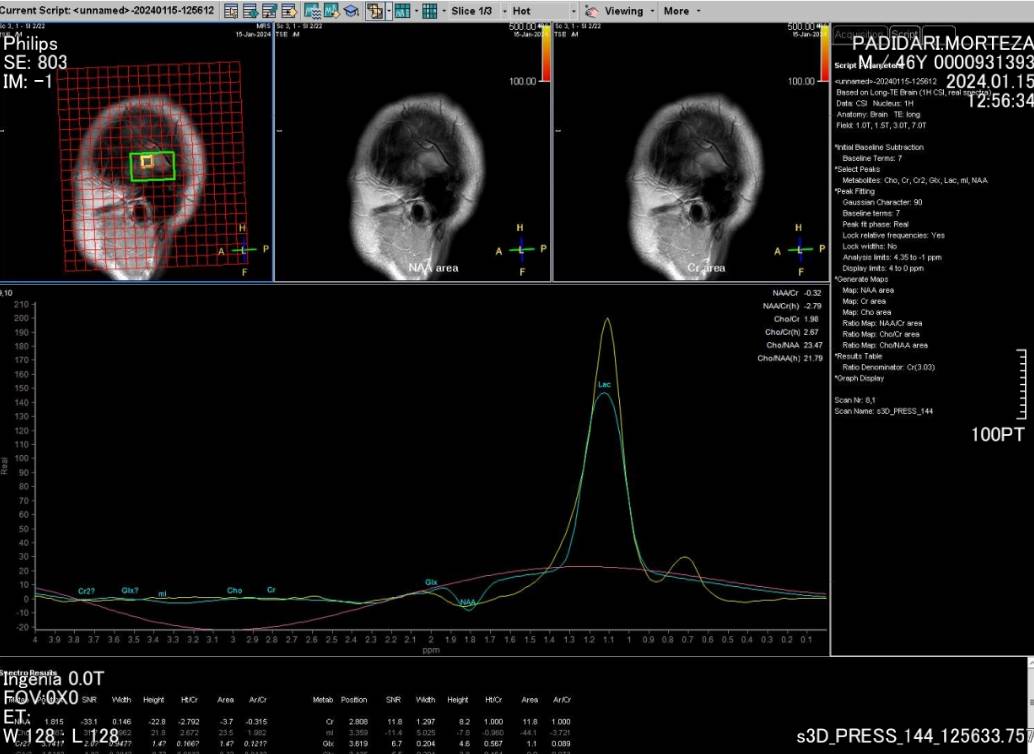

به گزارش پایگاه اطلاع‌رسانی دانشگاه عاوم پزشکی گیلان (وب‌دا)؛ دکتر ظهیر ریحانیان - رئیس مرکز آموزشی و درمانی پورسینا با اعلام این خبر گفت: اولین MRI پیشرفته به صورت DTI و MRS برای بیمار مبتلا به تومور مغزی در مرکز آموزشی و درمانی پورسینا انجام شد.

وی ادامه داد: سکانس‌های فوق برای تشخیص دقیق‌تر ضایعات مغزی و افتراق آن از سایر بیماری‌های مشابه کمک کننده می‌باشد همچنین در این شیوه نقشه برداری دقیق‌تر مغز برای انجام جراحی‌های پیشرفته بسیار حایز اهمیت است.